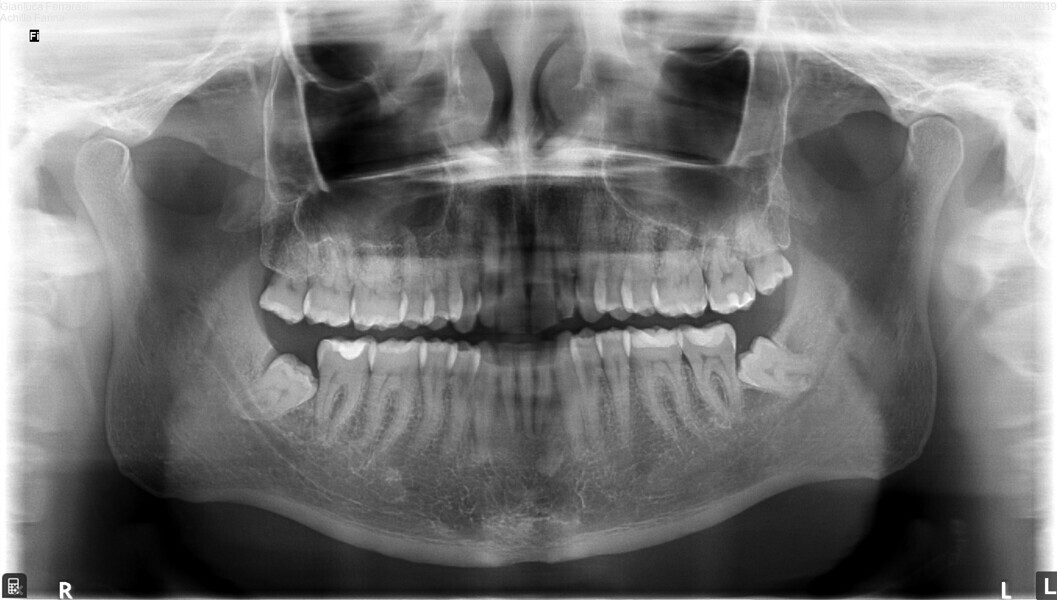

From the periodontal point of view, the patient showed a good attitude to oral hygiene, but crowding of the mandibular incisors made cleaning difficult in that area, causing plaque accumulation and localised gingival inflammation. The panoramic radiograph revealed the presence of the mandibular third molars and confirmed the absence of the mandibular right central incisor (Fig. 10).

Fig. 10: Pretreatment panoramic radiograph.